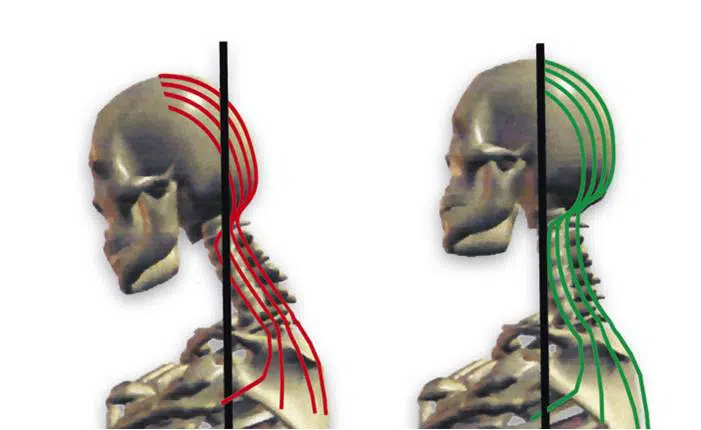

Uso del móvil y dolor cervical

Existe una relación sólida entre el uso del móvil y el dolor cervical. En las últimas décadas nos hemos habituado al uso continuo de este dispositivo; sin embargo, ¿se ha habituado igual de bien nuestra columna cervical?En Barcelona Quiropractic son cada vez más las personas, en edades tempranas, que padecen de problemas cervicales serios con […]

Pérdida de curvatura cervical y quiropráctica

La lordosis cervical es la curva que presentan las vértebras cervicales cuando son vistas de perfil. Cuando la altura anterior de los discos cervicales no es aproximadamente un 40% más que la altura de los discos en la parte posterior, es cuando se dice que existe una rectificación de esta, es decir, una pérdida de […]

¿Por qué tienes dolor de cuello y cómo puedes evitarlo?

El dolor de cuello o cervicalgia – en su nombre técnico – es un mal que, según los expertos, 7 de cada 10 personas lo sufre alguna vez en su vida. A veces es algo puntual, pero muchas veces se convierte en un dolor crónico. La cervicalgia se entiende como un indicio frecuente de trauma por una subluxación […]